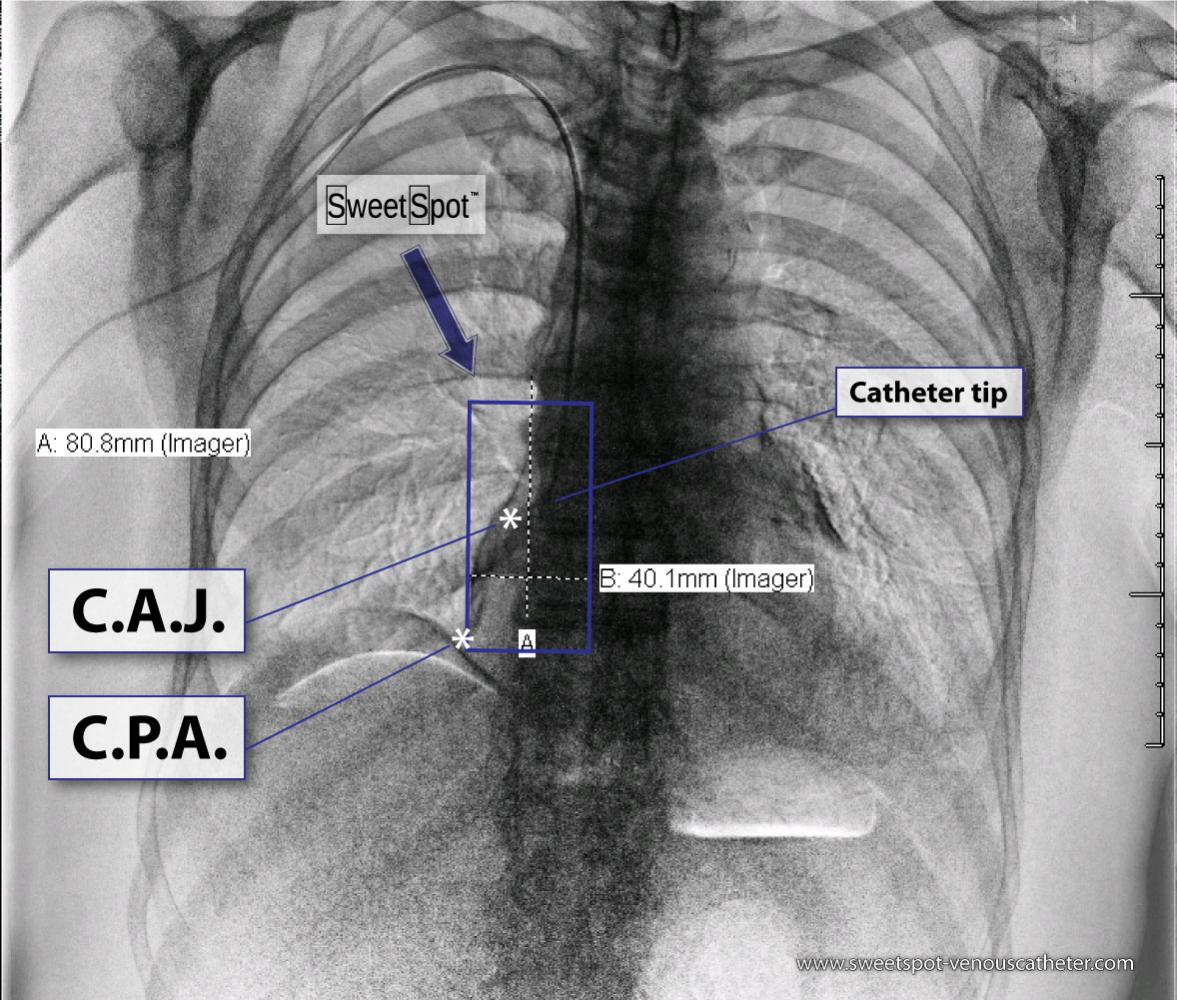

Figure - 03

Dual energy CXR. Another variation in Sweet Spot™ dimensions |